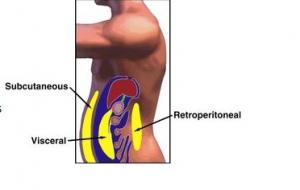

Actualité publiée il y a 10 années 3 moisBOISSONS SUCRÉES: Elles favorisent le développement de la graisse viscérale